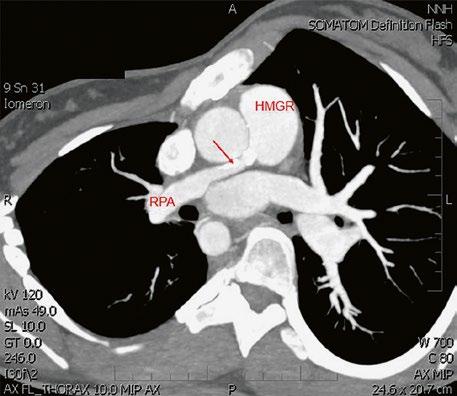

Obr. 45.40 CT angiografie, 8mm stenóza a deformace levé větve plicnice (šipka) po spojkové operaci podle BlalockaTaussigové v dětství LPA – levá větev plicnice, PA – kmen plicnice, RPA – pravá větev plicnice

Obr. 45.41 Uzávěr levé větve plicnice jako následek provedené spojky podle BlalockaTaussigové v dětství, CT angiografie